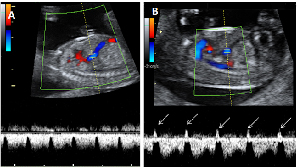

Ecografía Embarazo 2D y 3D Semana 12 - PRUEBAS DIAGNÓSTICAS